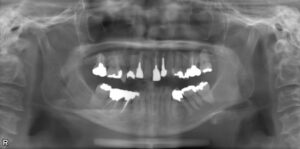

上下臼歯5本欠損症例

BEFORE AFTER 74歳女性/上下5本欠損/インプラント埋込手術 【治療内容】 右上第二小臼歯、第一、第二大臼歯…